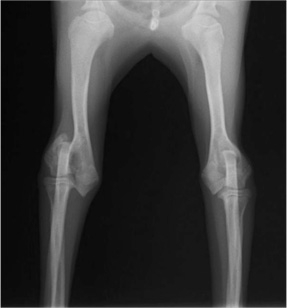

術前レントゲン

ペルシャ猫 11ヶ月齢 雄

他院にて左大腿骨遠位の成長板骨折(salter-harrisⅠ型)が認められており、治療相談を目的として来院。当院にて、キルシュナーワイヤーを用いたピンニングにより骨折部位の整復を行いました。術後の経過は良好で、現在も経過観察中です。